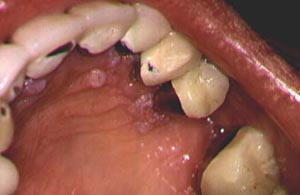

- قرحة أو تهيج أو كتلة أو رقعة سميكة في الفم أو الشفاه أو الحلق.

- بقعة بيضاء أو حمراء في فمك.

تجويف الفم. رقعة بيضاء أو حمراء على اللثة أو اللسان أو بطانة الفم. نمو أو تورم في الفك مما يؤدي إلى عدم ملاءمة أطقم الأسنان بشكل جيد أو أنها تصبح غير مريحة. ونزيف أو ألم غير عادي في الفم.